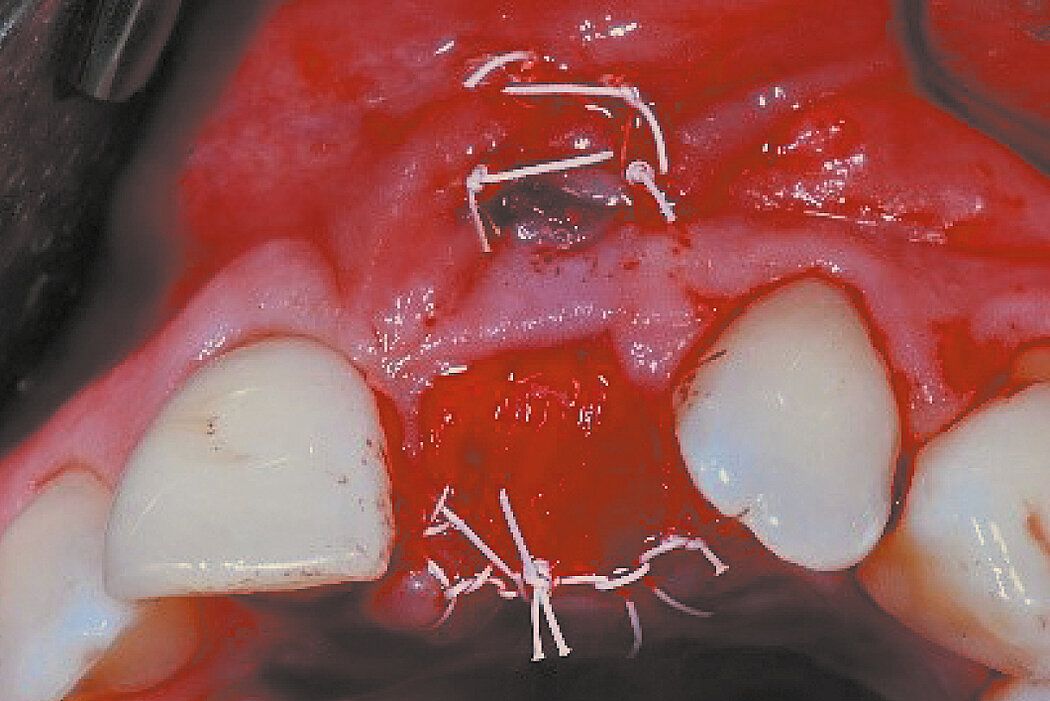

Replace a hopeless central incisor with a vertical fracture of the tooth root and buccal bone fenestration. The vestibulum already showed a fistula.

Conclusion

Ridge Preservation techniques are effective in minimising volume loss.